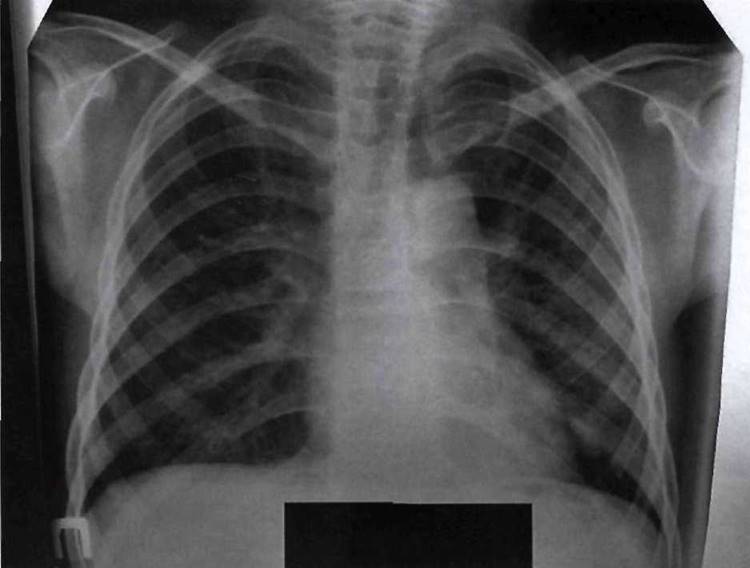

Рис. 11-2. Рентгенологические проявления рахита в период разгара.